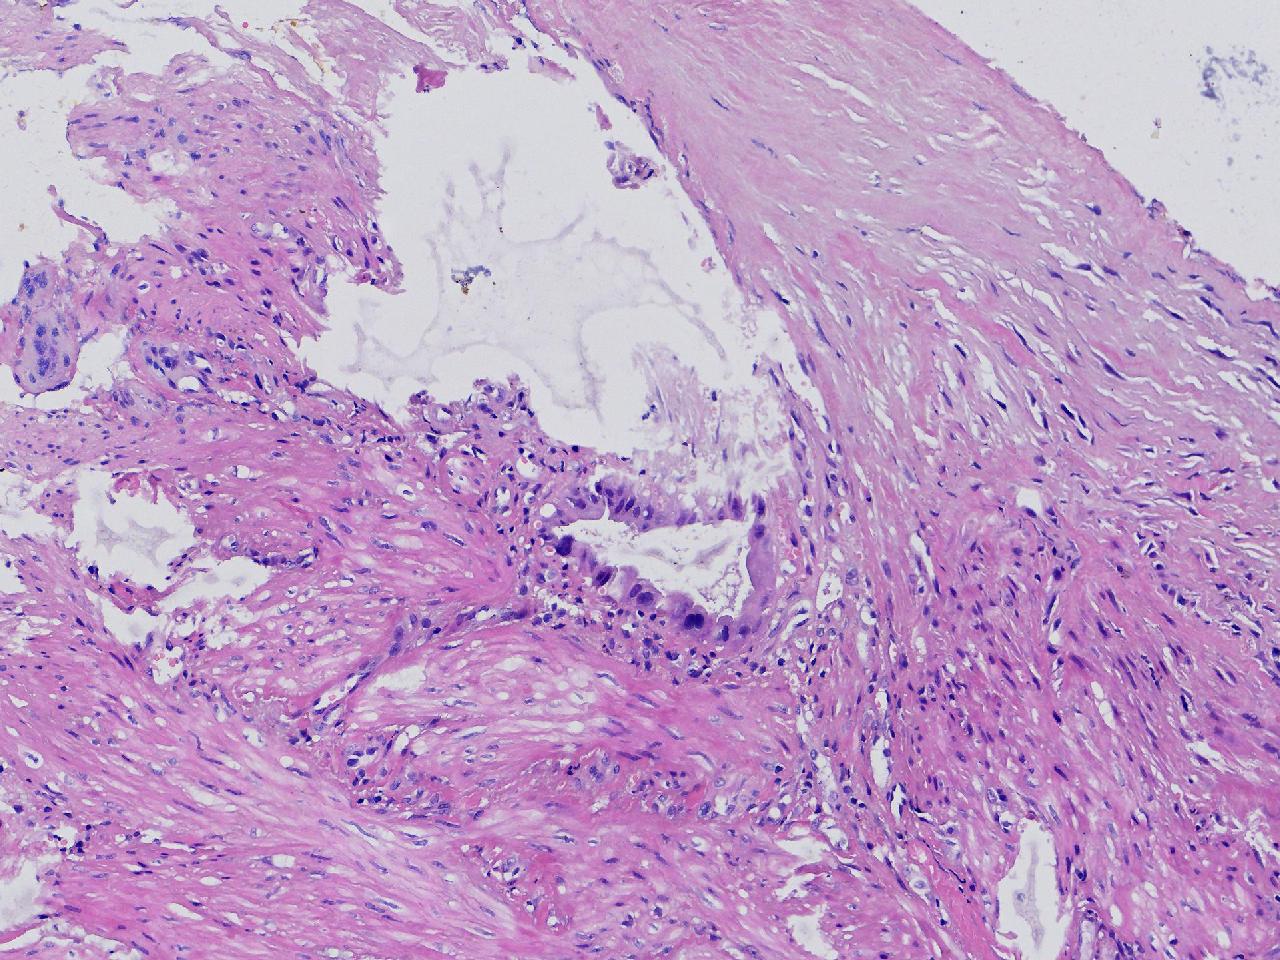

这些腺体有问题吗?

性别

女

年龄

38岁

临床诊断

胆囊结石伴慢性胆囊炎

一般病史

右上腹疼痛不适7年余,外科行胆囊切除。

标本名称

胆囊

大体所见

灰粉色胆囊一条,部分粘膜粗糙,腔内见泥沙样结石。

细胞有异型,标记看看

有异型,最好再补取几块。

这个蜡块重新制片,又多处取材制片,支持炎性反应性改变。 不支持肿瘤性。